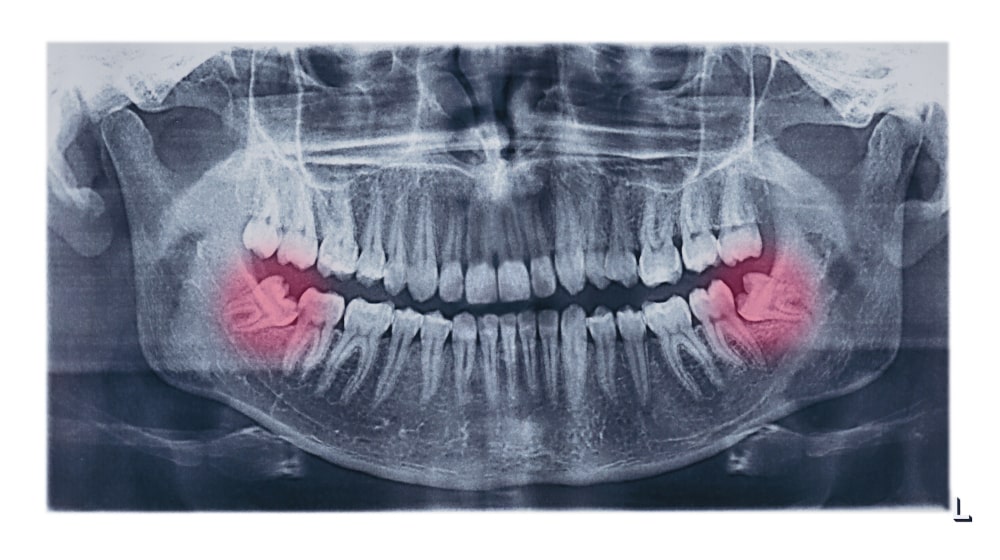

Impacted wisdom teeth typically require a more expensive surgical extraction. Here's how the procedure breaks down:

The complexity of the impaction significantly raises the price — especially if general anesthesia or a surgical suite is involved.